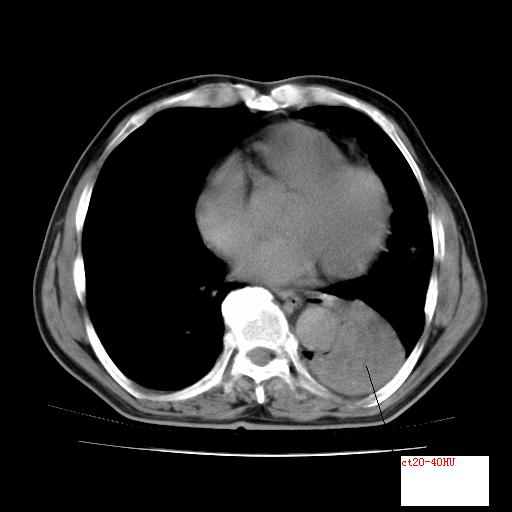

男,71岁,咳嗽,气喘10年,再发并咯血.胸片见气胸

考虑  左肺中心型肺癌伴阻塞性肺炎,肺不张,纵膈淋巴结肿大。慢支炎,肺气肿,左侧气胸肺压缩5%

左侧中央型肺癌伴纵膈淋巴结转移。

左肺中心型肺癌伴阻塞性肺炎,肺不张,纵膈淋巴结肿大

1)考虑左肺中心型肺癌伴阻塞性肺炎、左肺下叶肺不张、左侧肺气肿,纵膈淋巴结转移。2)左侧气胸(肺组织压缩约5%)。

左肺中心型肺癌伴阻塞性肺不张、肺气肿 。

1)考虑左肺中心型肺癌伴阻塞性肺炎、左肺下叶肺不张、左侧肺气肿,纵膈淋巴结转移。2)左侧气胸。